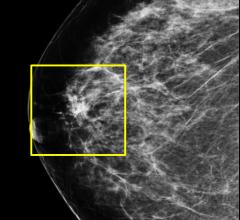

Despite decades of progress in breast imaging, one challenge continues to test even the most skilled radiologists ...

Viztek is one of the first picture archive and communications service (PACS) vendors to provide viewing capabilities for digital breast tomosynthesis (DBT) imaging. With the addition of this capability to Viztek’s Opal-Mammo software suite, hospitals and imaging centers now have a choice of the viewing software they select for use with their DBT system. Further, because the mammography suite offers integrated tracking software, facilities additionally benefit from the use of one workstation and an automated workflow for a faster, streamlined approach for mandatory MQSA reporting.

Forty-three of 44 providers interviewed by KLAS Research said they would buy tomosynthesis (3-D mammography) again despite the additional time it takes and the unpredictable reimbursement. This and other findings are available in the new KLAS report “Breast Tomosynthesis 2013: The Business Case.”